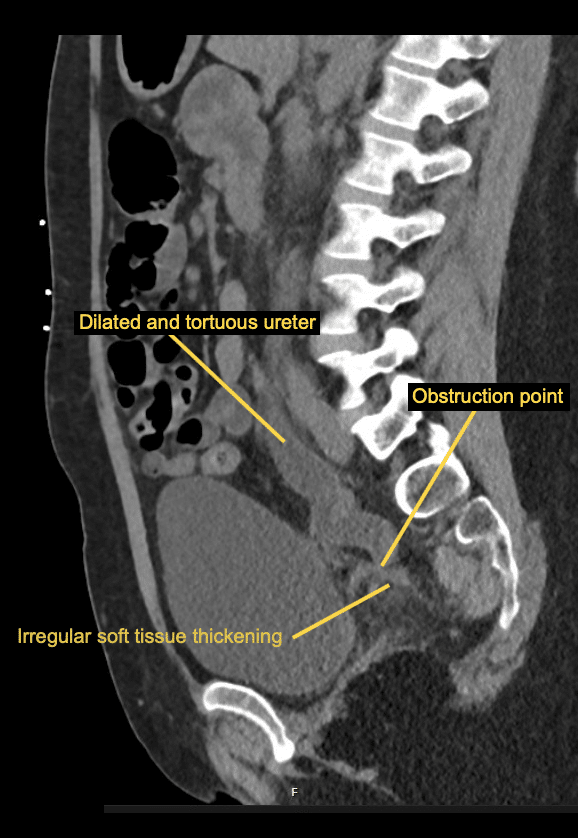

There is severe bilateral hydroureter and hydronephrosis.

The point of obstruction is at the vaginal vault level where there is irregular soft tissue thickening suggesting scarring. Distal to this the ureters return to a normal calibre.

There is cortical thinning of the kidneys bilaterally, more severe on the left side.

There is left perinephric and periureteric fat stranding.